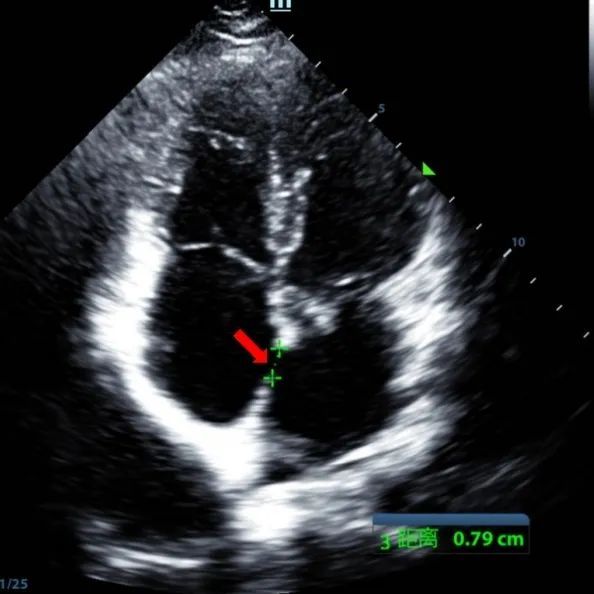

Un maschio di 9 anni con secundum ASD (7,5-7,9mm) è stato trattato utilizzando un sistema di occlusione da 12mm BDASD-I MemoSorb e un sistema di somministrazione 12F. Non sono state rilevate complicazioni o comorbidità prima della procedura.

Serial echocardiographic follow-ups showed stable device position and favorable cardiac remodeling. Gradual degradation confirmed the occluder's long-term safety and efficacy.